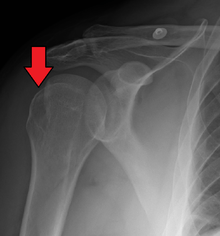

| Anterior shoulder dislocation on X-ray with a large Hill–Sachs lesion | |

A Hill–Sachs lesion, or Hill–Sachs fracture, is a cortical depression in the posterolateral head of the humerus. It results from forceful impaction of the humeral head against the anteroinferior glenoid rim when the shoulder is dislocated anteriorly.

The incidence of Hill–Sachs lesion is not known with certainty. It has been reported to be present in 40% to 90% of patients presenting with anterior shoulder instability, that is subluxation or dislocation.[2][3] In those who have recurrent events, it may be as high as 100%.[4] Its presence is a specific sign of dislocation and can thus be used as an indicator that dislocation has occurred even if the joint has since regained its normal alignment. The average depth of Hill–Sachs lesion has been reported as 4.1 mm. Large, engaging Hill-Sachs fractures can contribute to shoulder instability and will often cause painful clicking, catching, or popping.

Imaging diagnosis conventionally begins with plain film radiography. Generally, AP radiographs of the shoulder with the arm in internal rotation offer the best yield while axillary views and AP radiographs with external rotation tend to obscure the defect. However, pain and tenderness in the injured joint make appropriate positioning difficult and in a recent study of plain film x-ray for Hill–Sachs lesions, the sensitivity was only about 20%. i.e. the finding was not visible on plain film x-ray about 80% of the time.[5]